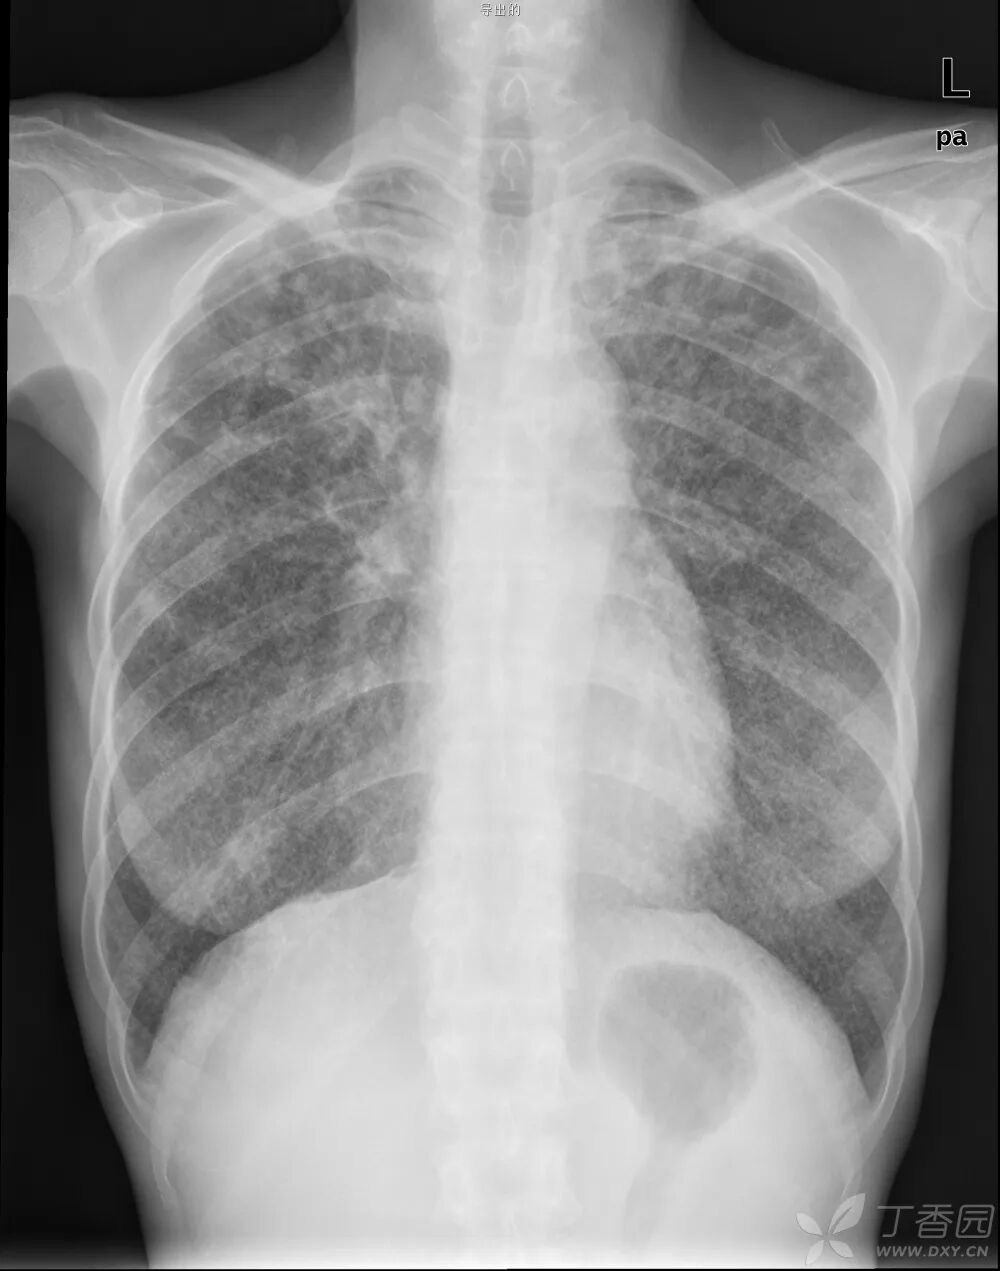

一、DR检查是在普通X光拍片的基础上,发展成为数字化X线拍片,通俗一点来理解,就是传统X光的进阶版,但本质还是差不多的,主要还是利用X射线的穿透性原理。虽然检查部位和普通X光拍片都一样,但DR的图像分辨率明显比X光高,放射线辐射剂量也降低了非常多。人体组织结构由不同元素组成,单位体积内的各种元素的总量就是密度,例如骨骼、钙化灶等听起来较为厚重的组织,所吸收的X光较多,穿透人体中余下的X线量较少,因此形成白色影像,也就是传说中的“高密度影”,像是呼吸道、胃肠道等听起来质地疏松的部位,所吸收的X光较少,在影像学上呈现的是黑色影像,即“低密度影”。DR成像环节少,速度也快,图像清晰细腻,医生可根据根据自身需要,获得更多的诊断信息。DR图像动态范围广,有很宽的曝光宽容度,因而容许拍摄中的技术误差,即使在一些曝光条件难以掌握的部位,也能获得很好的图像。总体来说,DR是最传统也是最低价的影像检查,是很多疾病的首选检查。

DR最常用于人体胸部及骨骼摄片,也可拍摄其他部位,例如腹部、牙齿、头颅等。使用人群较广,可以进行全身各部位检查,曝光后10秒就可获得数字影像,成像速度快,且价格便宜,极大提高了工作效率,方便临床重症、急症患者的诊治。但DR受制于深浅组织影响的互相重叠和隐藏,有时需要多次或多角度的拍摄才能看清。